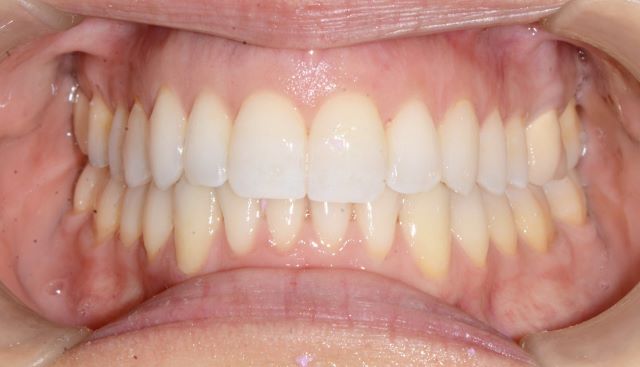

מנשך תקין

מנשך שבו השיניים בלסת העליונה ובלסת התחתונה,נפגשות האחת מול השנייה(ראה תמונות מצורפות).